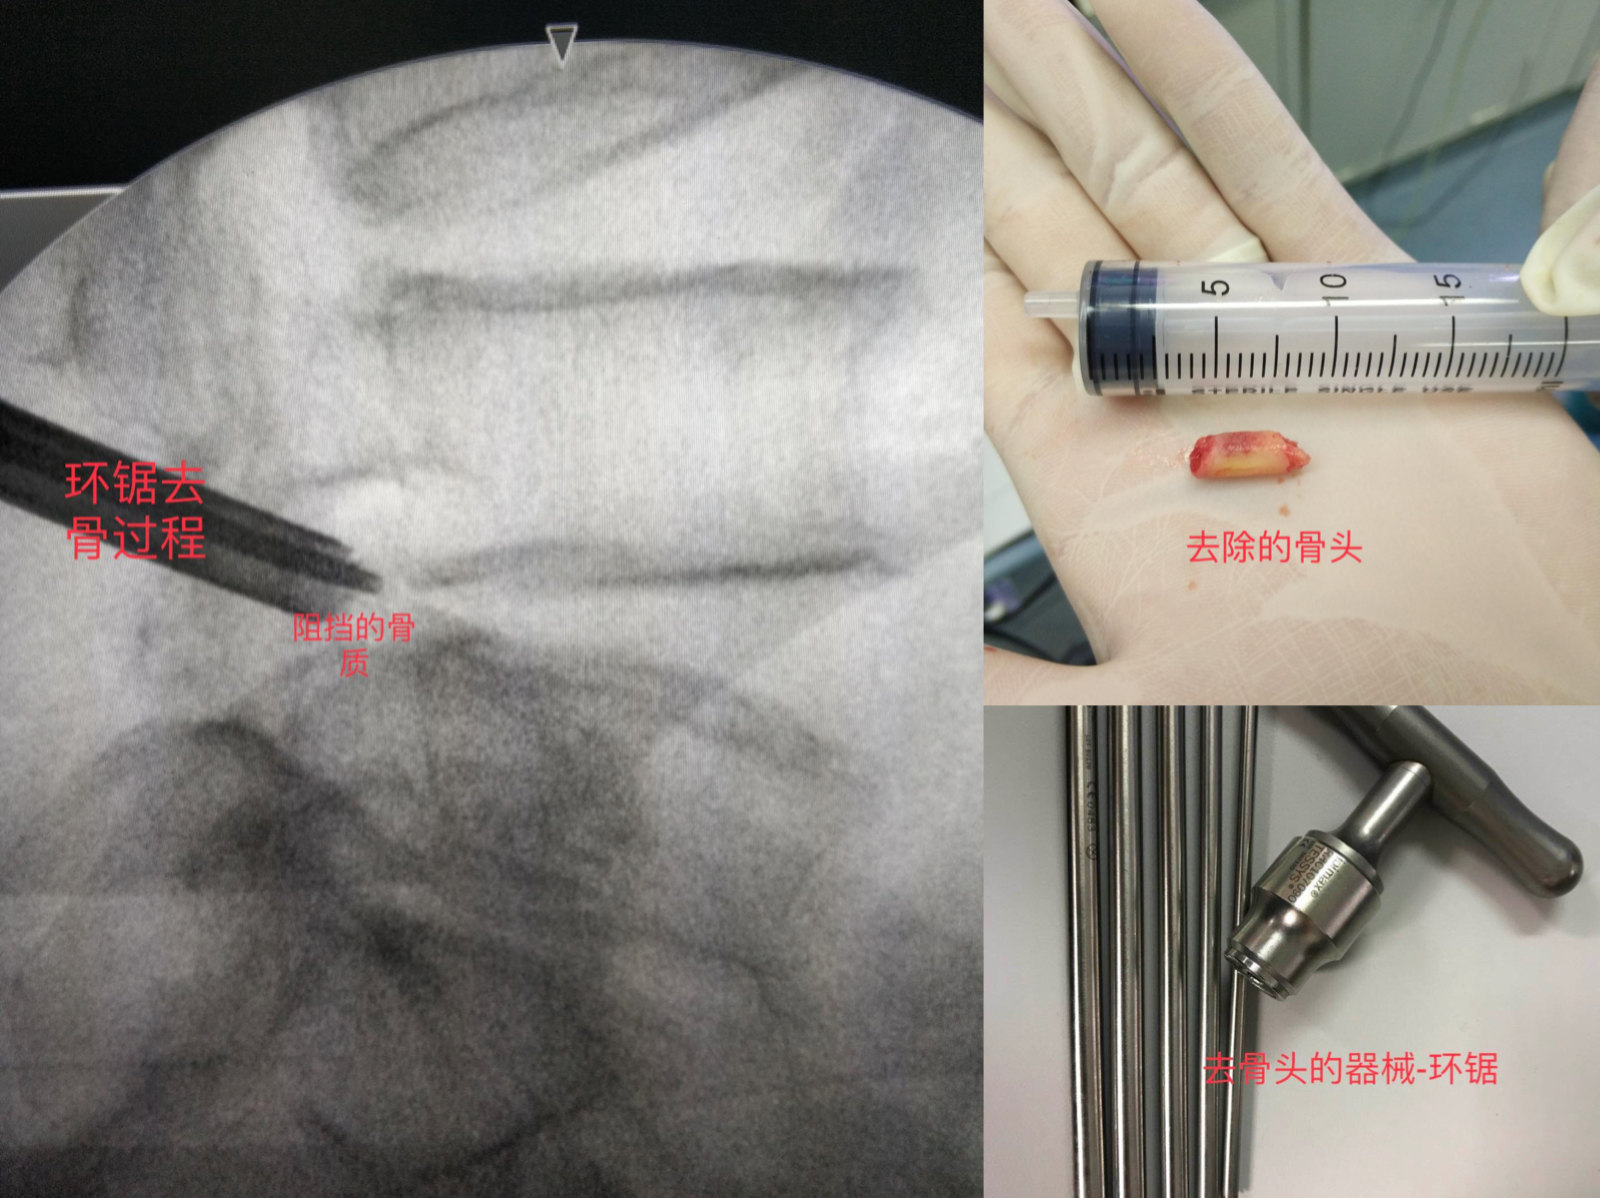

打完麻药后手术就正式开始,我们会选用非常细的穿刺针从皮肤进针点穿刺到突出椎间盘,但是穿刺过程中会有椎间孔区的关节骨质阻挡,所以我们常规就将穿刺针顶到阻挡的关节骨质表面,然后用器械去除阻挡的骨质。见下图。

关节去骨成型

穿刺过程由于关节骨质阻挡,无法顺利到达椎间盘,因此穿刺针顶到阻挡的骨质后,我们会用器械去掉阻挡的骨质。去掉的骨质总体量很小,对身体无影响。